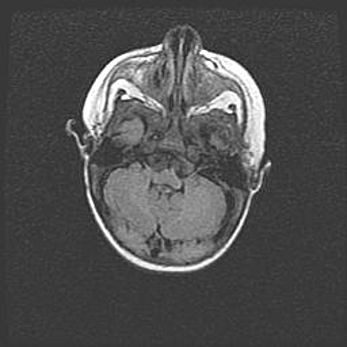

Подострая гематома правой гемисферы мозжечка.

Наружная гидроцефалия.

Возраст: 15 дней

Вес: 3100 г

Пол: женский

Окружность головы: 37 см

Срок гестации: 35-36 недель

При открытой наружной форме гидроцефалии у новорожденных расширяются и переполняются субарахноидные пространства.

Кровоизлияния в мозжечок имеют две клинико-анатомические формы: полушарные гематомы и кровоизлияния в червь.

К появлению этой патологии может привести: повреждения головного мозга, возникающие в результате асфиксии и гипоксии плода при беременности, или травмы во время родов. Редко гематома мозжечка может быть результатом первичной коагулопатии и сосудистой мальформации, диссеминированном внутрисосудистом свертывании, изоиммунной тромбоцитопении.